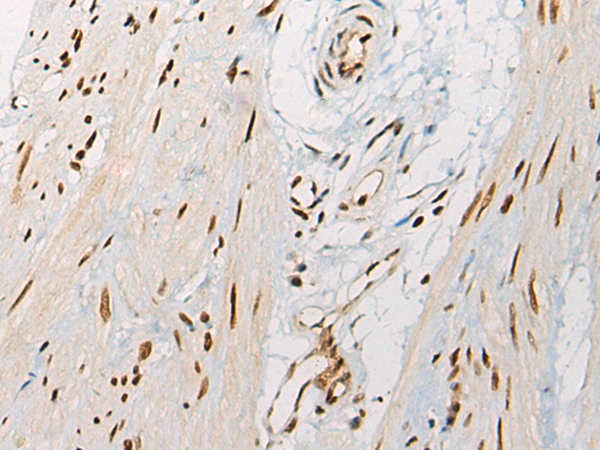

分类: 科研抗体货号: P05975别名: VGL3; VGL-3应用: IHC反应种属: Human, Mouse